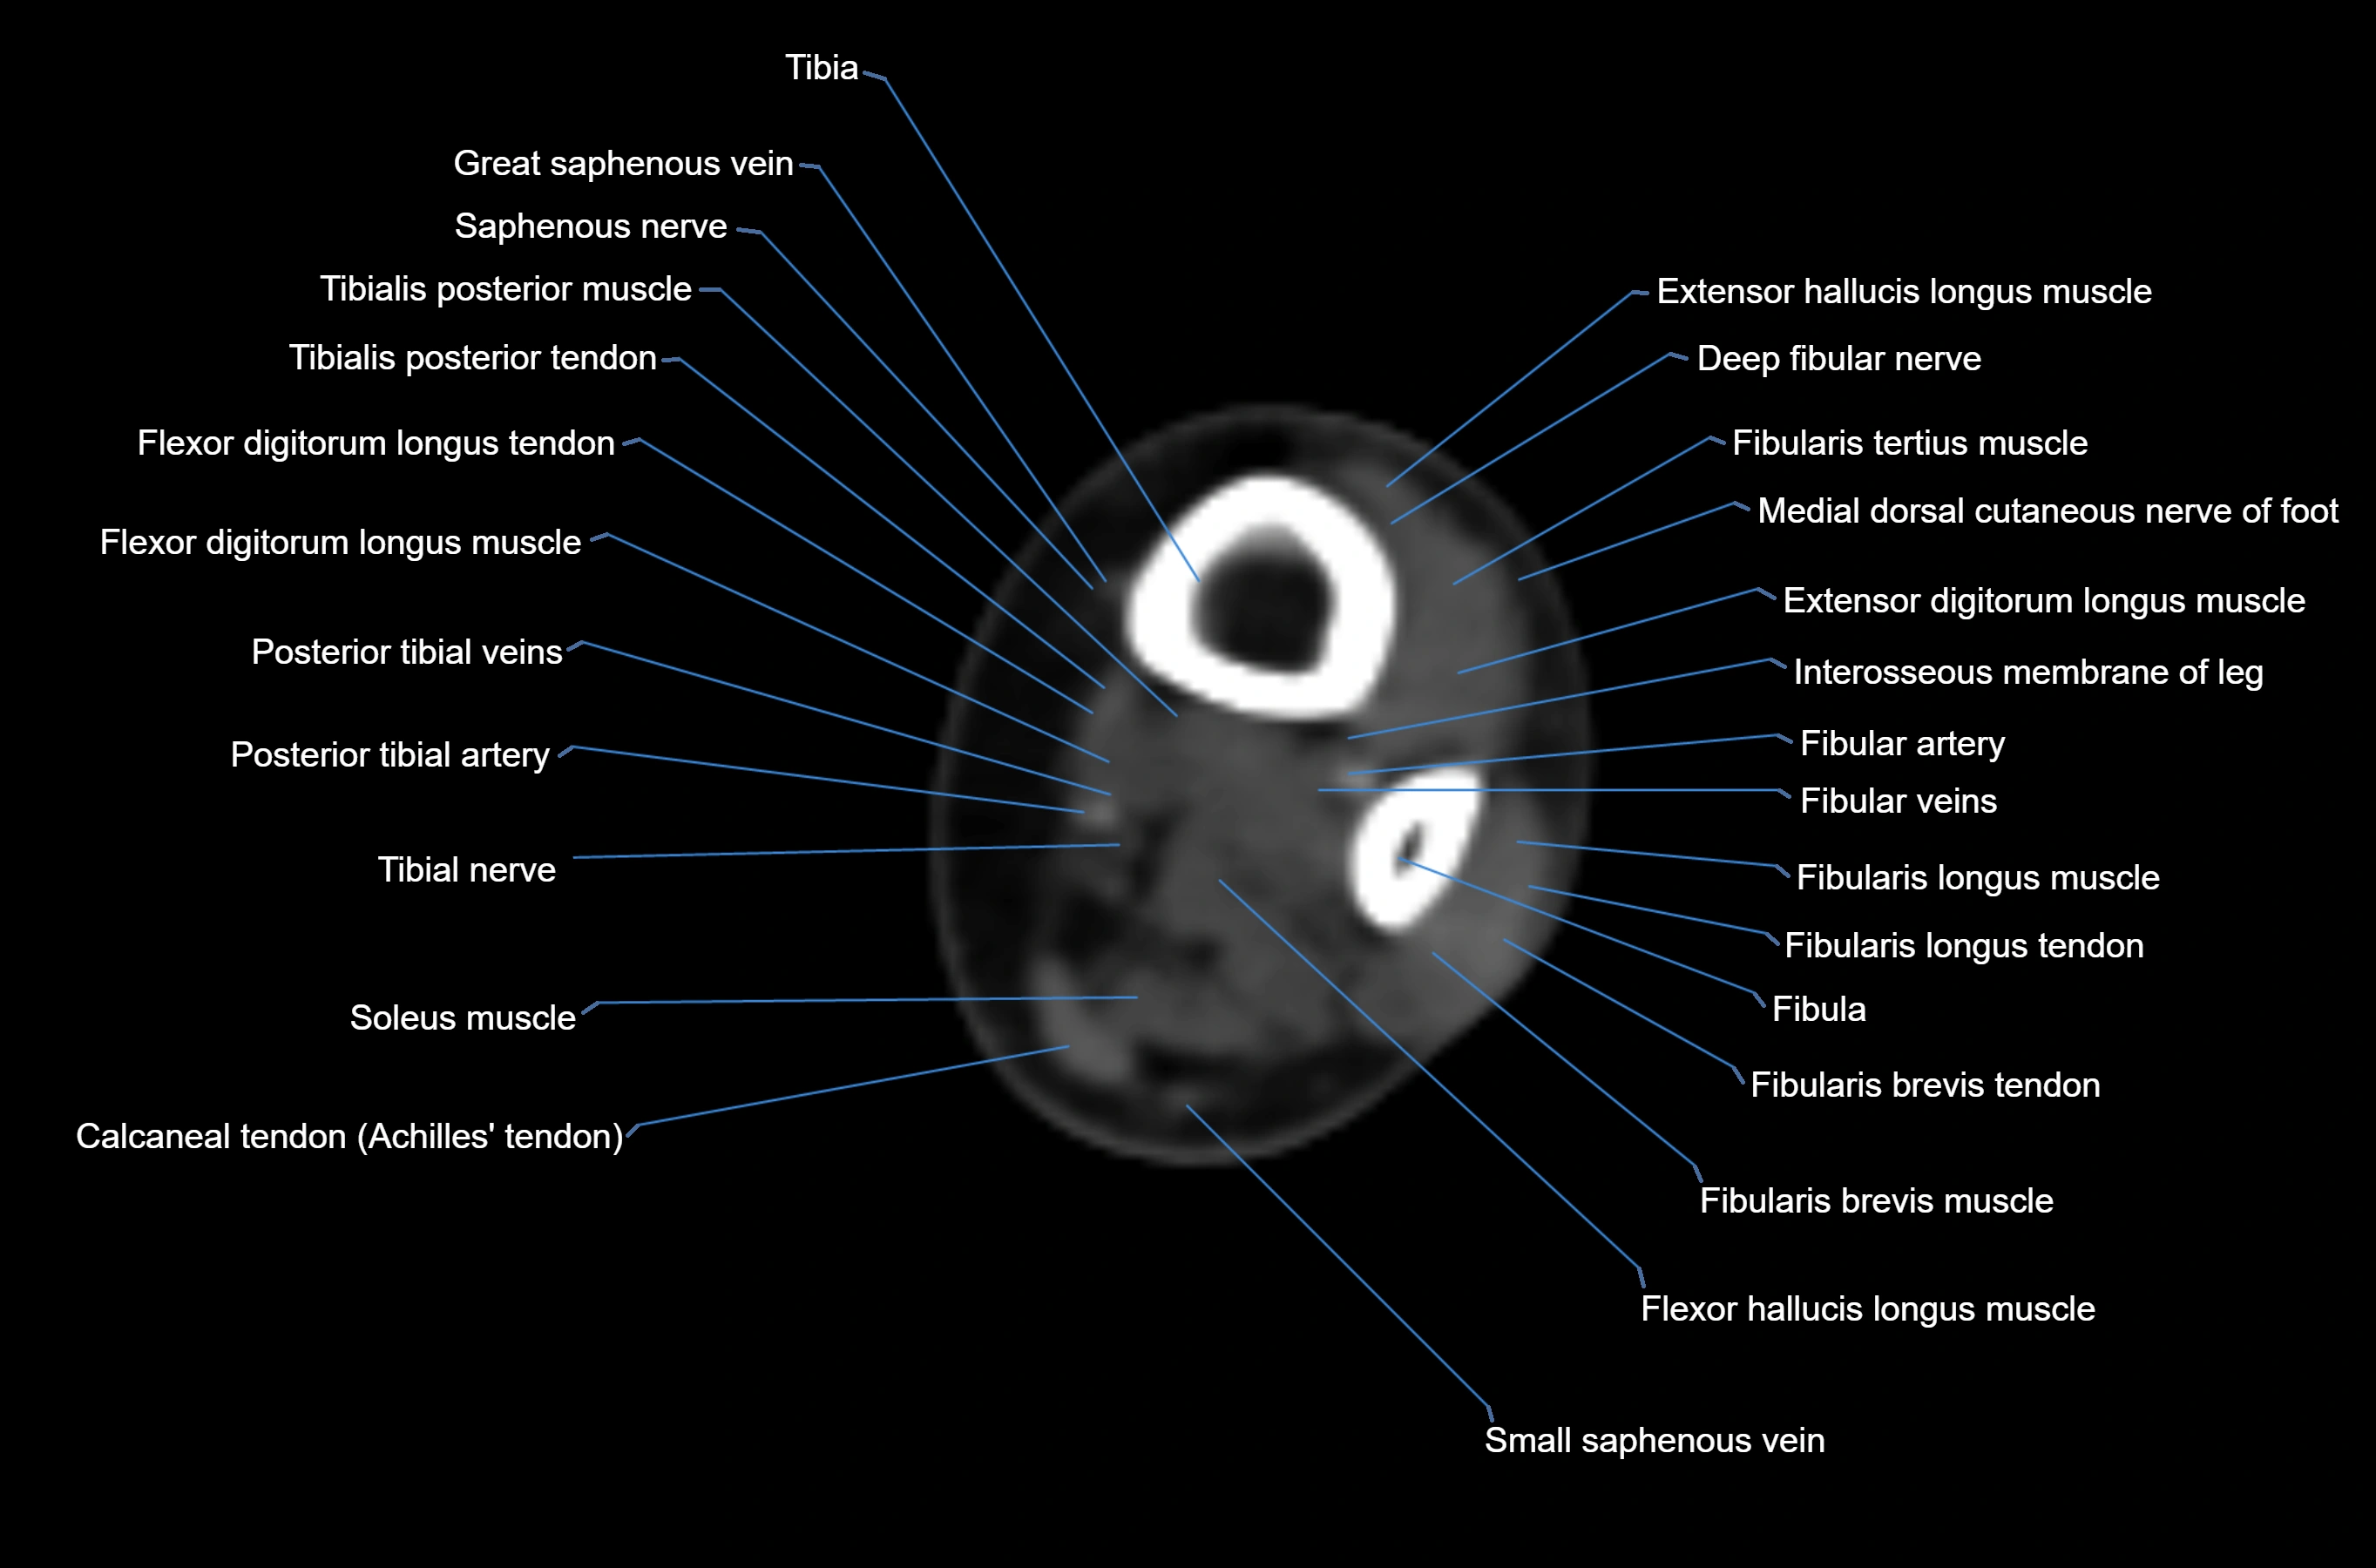

MRI image